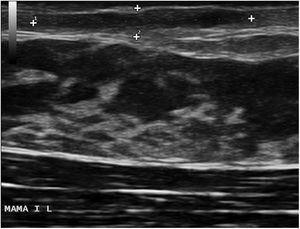

The physical examination revealed an elongated and erythematous indurated area in the area of the areola of the left breast that was painful to touch (Fig. 1). Ultrasound revealed a longitudinal hypoechoic band-like image (15 × 2.4 × 6 mm) in the superficial dermis (Doppler negative) compatible with a fistulous tract (Fig. 2). Based on these findings, the patient was diagnosed with mammillary fistula and prescribed treatment with intralesional triamcinolone, which led to clinical and ultrasound resolution of the lesion. No recurrences were observed during the following 6 months (Fig. 3).